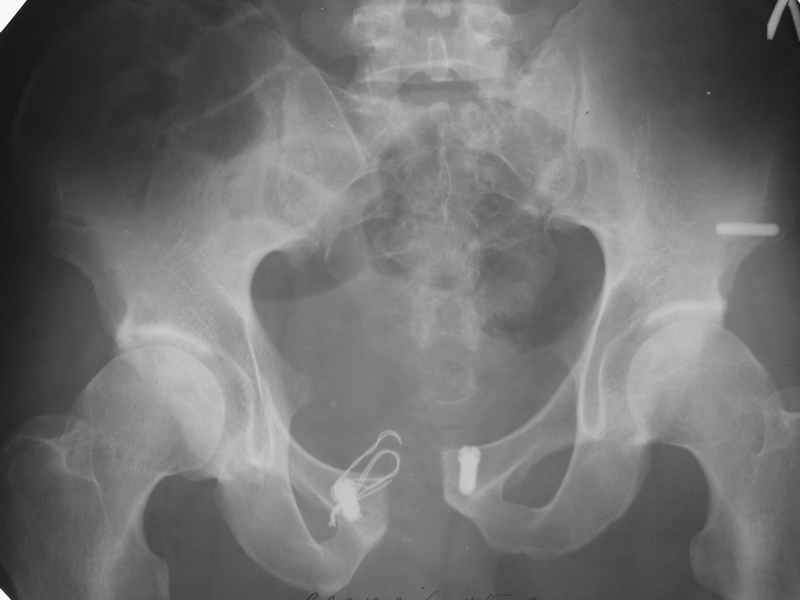

Что-то такое подразумевается? См. приложение...

Но IMHO считаю, что недостатком применения пластин в этой области является именно не физиологическая стабилизация, которая нередко приводит к перелому оных или расшатыванию винтов. Таких картинок ни у кого нет.

AC> Что-то такое подразумевается? См. приложение...

Александр Николаевич при всём моём глубоком уважении, несколько формальный подход. Серкляж разорван, так и на локтевых отростках рвут и на бедре пластины гнут, однажды даже видел погнутый аппарат Илизарова, но там д.т.п. было.